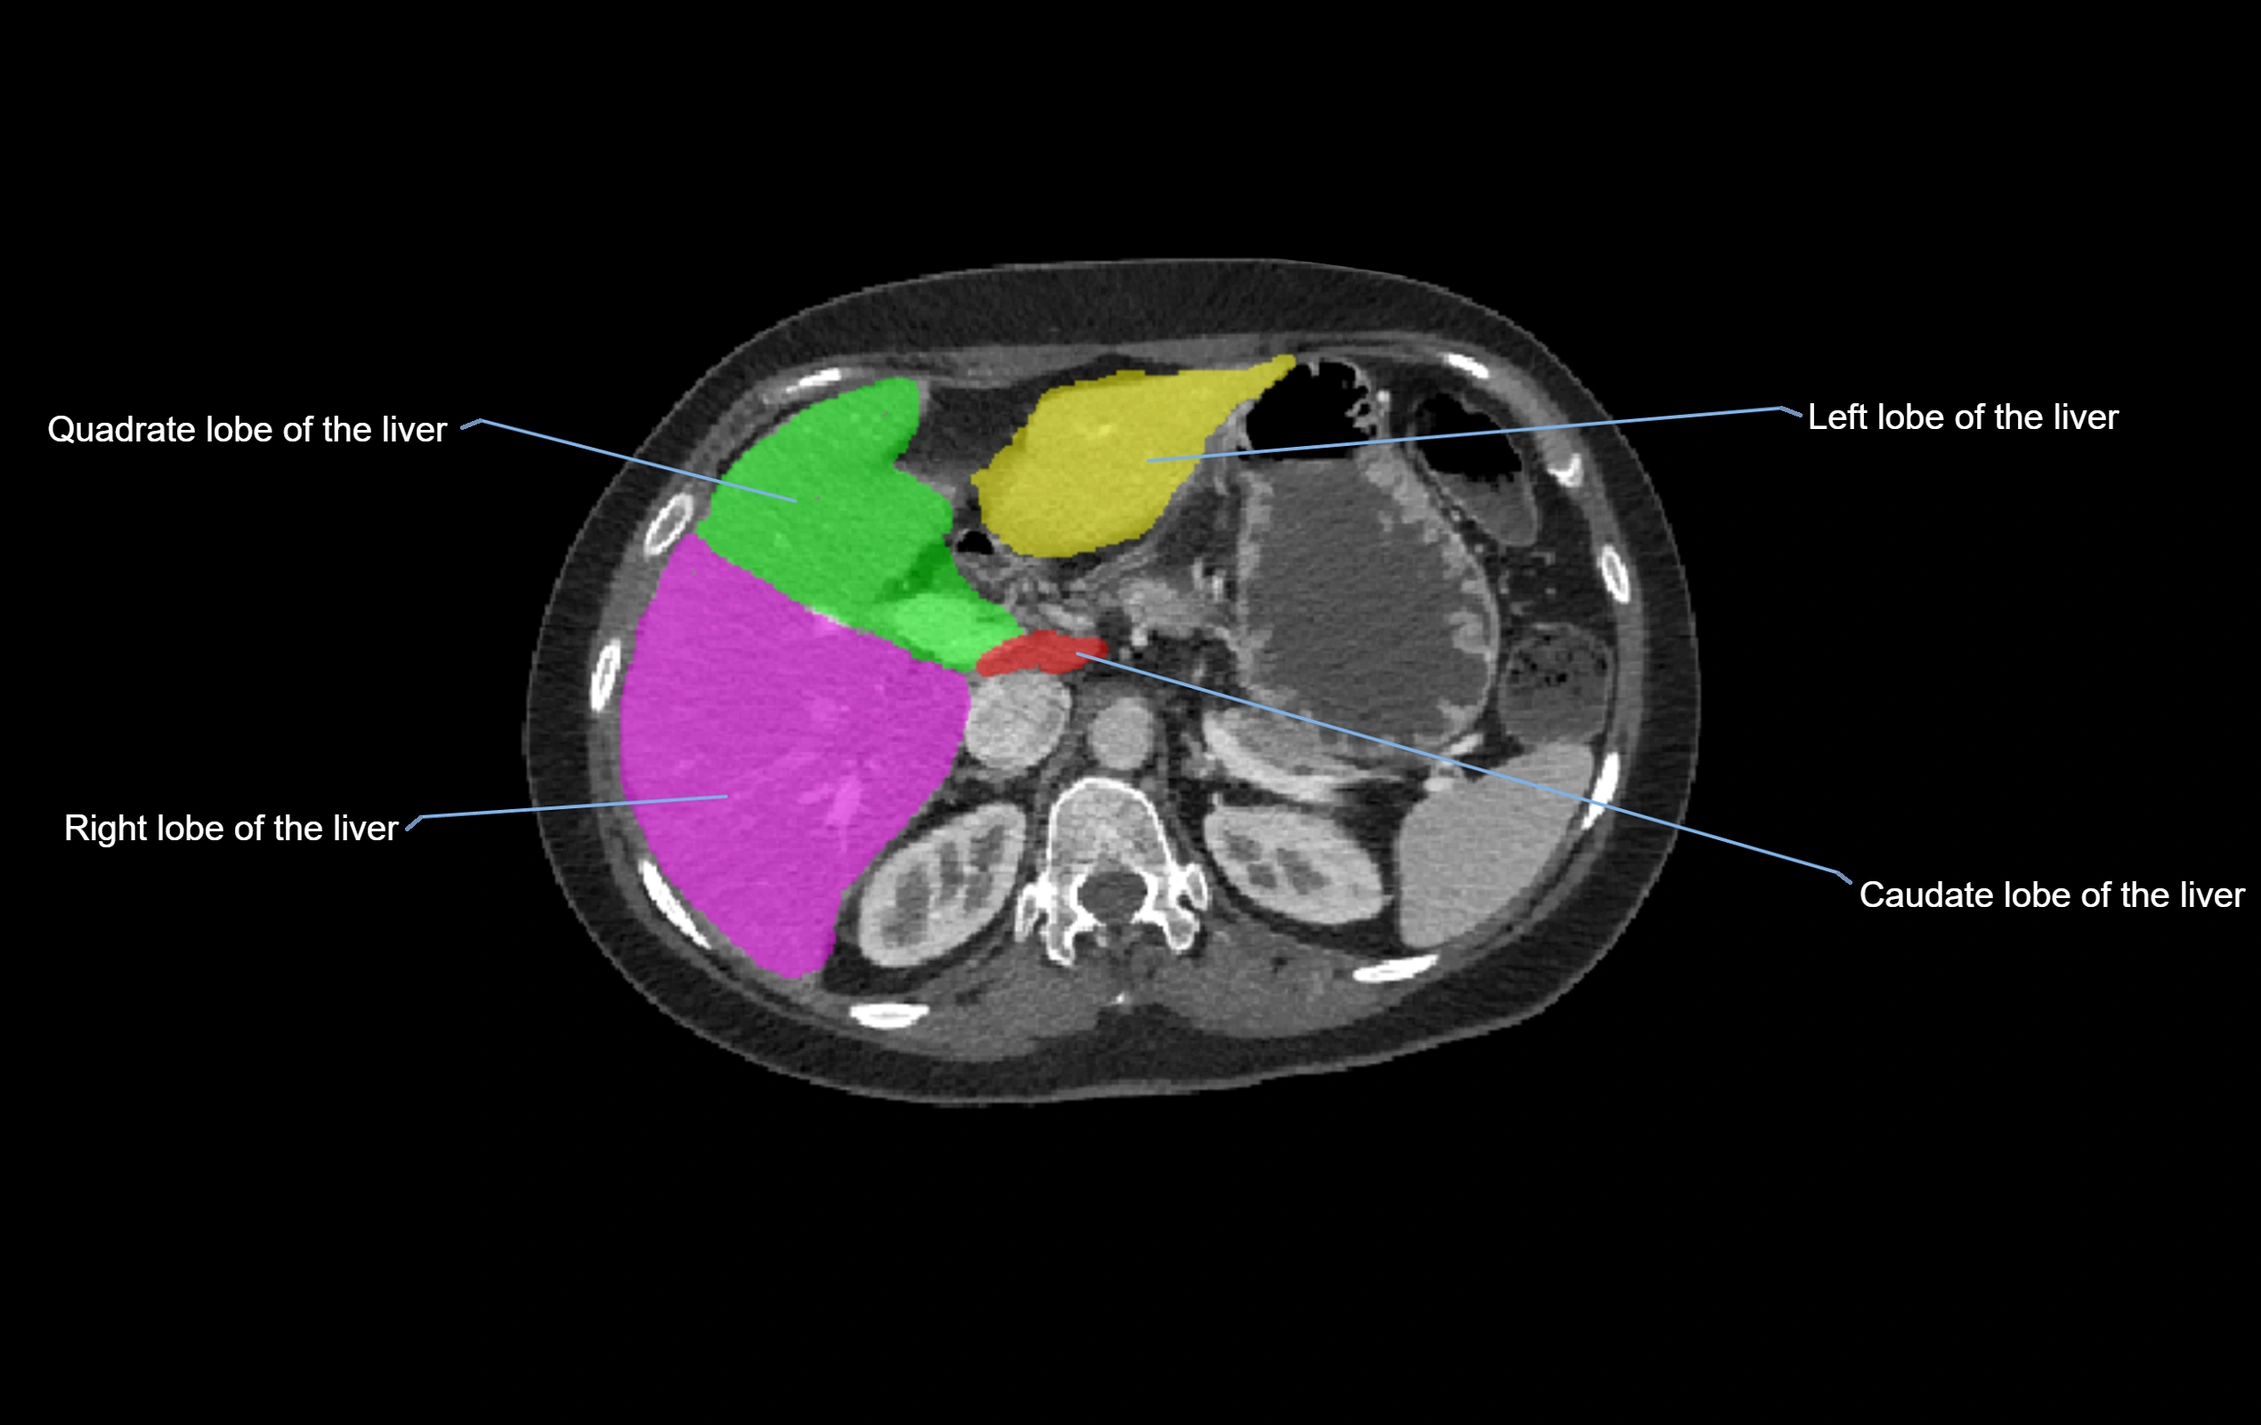

CT Appearance

CT Pre-Contrast:

• Caudate lobe appears as a soft-tissue density, isodense to the rest of the liver

• Enlargement may be appreciated in cirrhosis or Budd–Chiari syndrome

CT Post-Contrast:

• Homogeneous enhancement in the portal venous phase, similar to rest of liver

• Independent venous drainage into the IVC may be visualized

• Lesions follow characteristic CT enhancement patterns (HCC: arterial hyperenhancement with washout; hemangiomas: peripheral nodular enhancement with centripetal fill-in)

CT Venous Phase (functional significance):

• Caudate lobe often enhances relatively more than other lobes in Budd–Chiari syndrome, due to preserved venous outflow

CT Image

image